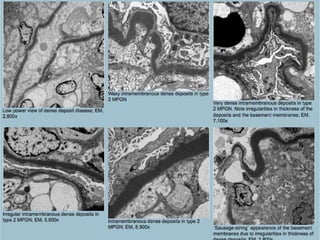

(MPGN), type II (Dense deposit

disease)

• Type II membranoproliferative

glomerulonephritis (MPGN) is a distinct and

very rare form of MPGN characterized by

dense intramembranous deposits (hence the

synonym “dense deposit disease”) with C3

reactivity by IF; the disease is associated with

serum C3 nephritic factor and is characterized

by profound decrease in serum C3 levels.

• Histopathology:

• Mesangial prominence and hypercellularity

• Capillary loops are thickened and may exhibit a ribbon-like

appearance due to intramembranous deposits; double

contours are not a dominant feature

• Crescents and proliferative changes are rare but may be

present

• Immunofluorescence:

• Striking C3 positivity along the capillary loops and in the

mesangium, in the absence of immunoglobulins and other

complement components (C4 and C1q)

• Electron microscopy:

• Visceral epithelial cells: Focal, sometimes marked

effacement of visceral epithelial cell foot processes

• Glomerular basement membranes: “Sausage-string”

appearance due to alternating normal with thickened

segments containing very dense and homogeneous

intramembranous deposits

• Glomerular endothelial cells: Show loss of

fenestrations and other non-specific changes; they do

not contain tubuloreticular structures

• Mesangium: Deposits of similar texture and quality to

those seen in the GBM are also seen in the mesangium